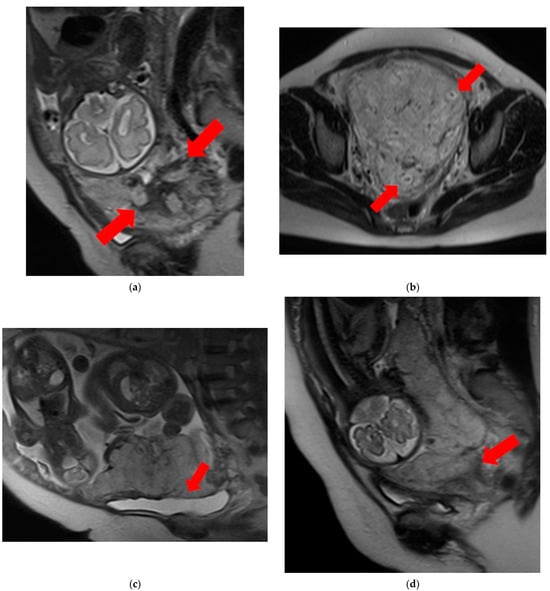

- T2 dark bands: dark lines on T2-weighted images showing nodular or linear patterns from the uterus to the placenta (Figure 1a).

Figure 1. Examination of magnetic resonance imaging features in the spectrum of placenta accreta with placenta previa disorder reveals the following characteristics: (a) T2 dark bands, indicating areas of low signal intensity on T2-weighted images (arrows). (b) Placental heterogeneity, depicting varied signal intensity within the placenta due to recurrent hemorrhages or lacunae (arrows). (c) Placental bulge, characterized by the protrusion of the lower segment of the uterus caused by the mass effect of the placenta, typically towards the bladder (arrow). (d) Placental cervical protrusion, showcasing the extension of placental tissue into the cervical canal (arrow). (e) Abnormal vascularization of the placental bed, featuring noticeable vessels in the placental bed with disruption of the uteroplacental interface (arrows). (f) A focal exophytic mass, indicating the protrusion of placental tissue through the uterine wall and beyond (arrows). (g) Myometrial thinning, demonstrating a reduction in myometrial thickness over the placenta to <1 mm or even making it invisible (arrow). - Placental heterogeneity: uneven signal intensity observed inside the placenta, often due to repeated bleeding (Figure 1b).

- Placental bulge: lower uterine protrusion caused by the placenta, usually toward the bladder (Figure 1c).

- Placental cervical protrusion sign: placental tissue sticking to the cervical canal (Figure 1d).

- Abnormal vascularization of the placental bed: disturbed blood vessels in the placental bed affecting the uteroplacental connection (Figure 1e).

- Focal exophytic mass: placental tissue extending through the uterine wall (Figure 1f).

- Myometrial thinning: Thinning of the uterine muscle over the placenta, sometimes becoming nearly invisible (Figure 1g).